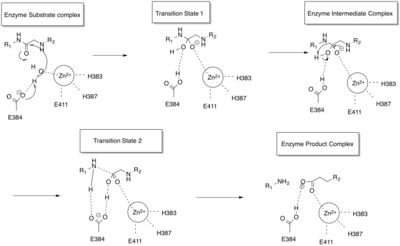

ACE is a zinc metalloproteinase.[13] The zinc center catalyses the peptide hydrolysis. Reflecting the critical role of zinc, ACE can be inhibited by metal-chelating agents.[14]

The E384 residue is mechanistically critical. As a general base, it deprotonates the zinc-bound water, producing a nucleophilic Zn-OH center. The resulting ammonium group then serves as a general acid to cleave the C-N bond.[16]

The function of the chloride ion is very complex and is highly debated. The anion activation by chloride is a characteristic feature of ACE.[17] It was experimentally determined that the activation of hydrolysis by chloride is highly dependent on the substrate. While it increases hydrolysis rates for e.g. Hip-His-Leu it inhibits hydrolysis of other substrates like Hip-Ala-Pro.[16] Under physiological conditions the enzyme reaches about 60% of its maximal activity toward angiotensin I while it reaches its full activity toward bradykinin. It is therefore assumed that the function of the anion activation in ACE provides high substrate specificity.[17] Other theories say that the chloride might simply stabilize the overall structure of the enzyme.[16]